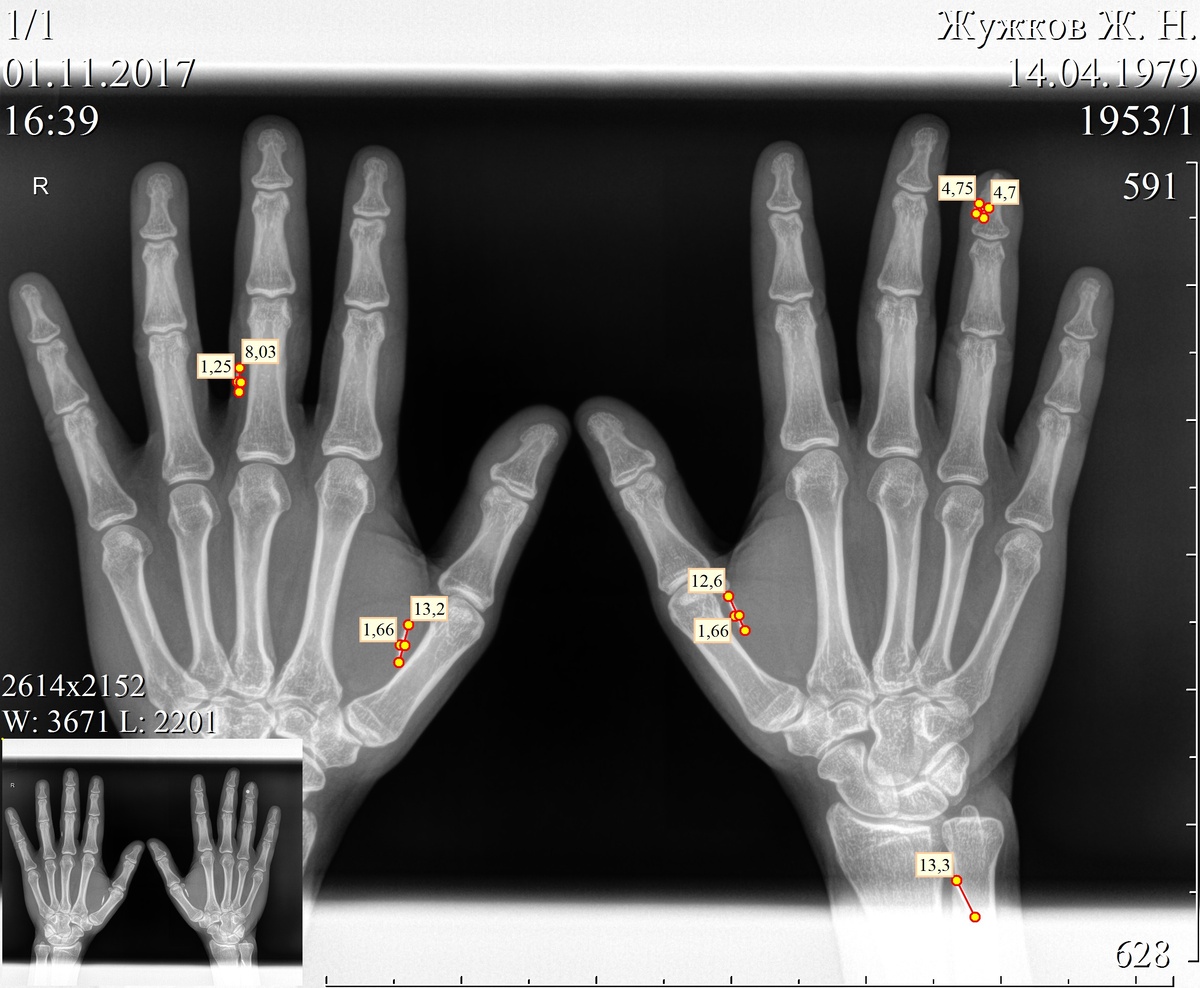

Как выглядят электронные импланты в руках

Рентгеновский снимок моих ладоней Вот так нагляднее: магнит и четыре колбы Viva la RFID!

Рентгеновский снимок моих ладоней

Вот так нагляднее: магнит и четыре колбы

Viva la RFID!